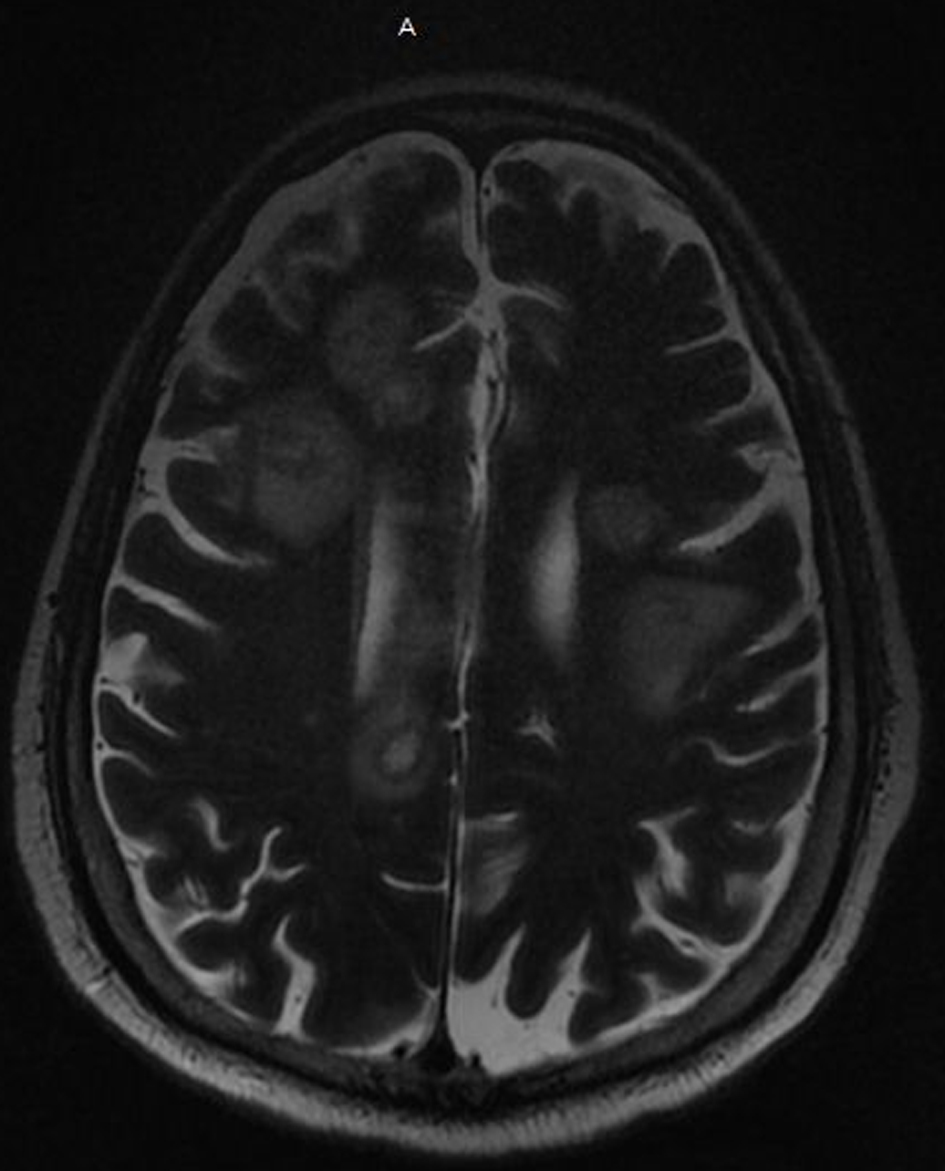

On his 11th week of hospitalization a code stroke was called for acute right-sided weakness and altered mental status. Computed tomography (CT) of the head was performed and showed multiple hypodensities suspicious for stroke versus possible metastasis. Subsequent magnetic resonance imaging (MRI) of the brain showed innumerable peripheral enhancing mass lesions, highly suspicious for multifocal metastases (Fig. 1). He was ultimately intubated for airway protection and sent to the neurological intensive care unit. Due to high suspicion for malignancy he had an abdomen/pelvis CT which was negative for a mass. As the patient’s mental status did not improve, his family met with palliative care and his code status was changed to “do not resuscitate”. During this same week, he had a pulseless electrical activity (PEA) cardiac arrest and expired.

![]() Click for large image | Figure 1. MRI of the brain with and without contrast shows innumerable peripheral enhancing mass lesions highly suspicious for multifocal metastases. MRI: magnetic resonance imaging. |